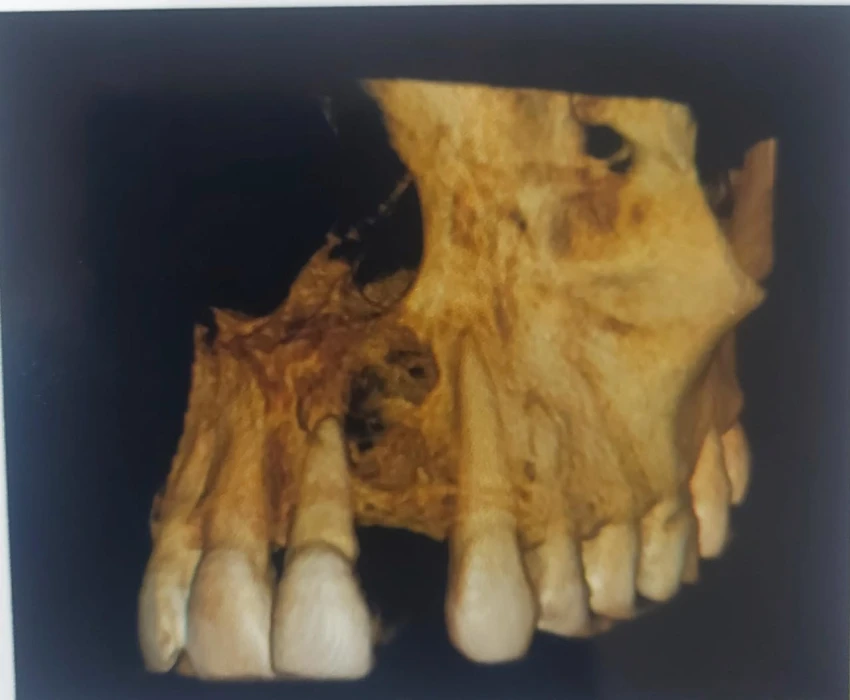

Investigation- CBCT, Viral markers, CBC, BT, CT

DIAGNOSIS- irreversible pulpitis with periapical granuloma.

TREATMENT- Faulty prosthesis is removed in respect to 22, with the help of tapered fissure. Access Opening is done' in respect to 21, under La. Working length is determined . Canals are prepared using Hyflex CM and obturated using Gutta percha using lateral condensation. Microperiosteal flap is raised. Window preparation irt 21 , periapical curretage apicoectomy is done irt 21 followed by retrograde filling with bioceramic. Cavity is filled with bone graft. Sutures placed.